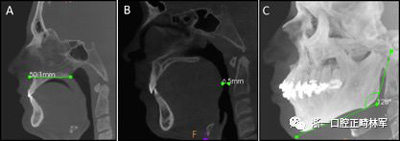

使用CS 3D成像軟件(版本3.4.3; Care-stream Health,Rochester,NY)進(jìn)行線性和角度測量。線性指標(biāo)包括鼻前后棘間距(ANS-PNS距離),咽腔最短距離(最短距離),咽腔C1的前后距離(APC1),咽腔C1的側(cè)壁間距離(LLC1),咽腔C2的前后距離(APC2),咽腔C2的側(cè)壁間距離(LLC2),咽腔C3的前后距離(APC3),咽腔C3的側(cè)壁間距離(LLC3),咽腔-會厭基底的前后距離(AP會厭),咽腔-會厭基底的側(cè)壁間距離(LL會厭),下頜骨兩側(cè)間的距離(L下頜骨),下頜骨的前后距離(AP下頜骨),舌骨兩側(cè)間的距離(L1舌骨)以及舌骨的前后距離(AP舌骨)。下頜骨前后角度的測量(下頜AP角),下頜橫角(TA下頜骨)和舌骨橫角(TA舌骨)。測量結(jié)果列于表I和圖1-4中。

圖1. A,ANS-PNS距離; B,最短距離; C,下頜AP角。